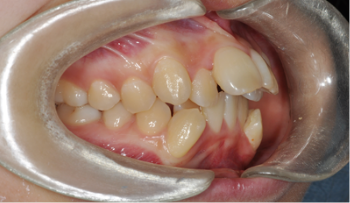

​​​​Case 05. 비수술 교정 치료

아래턱이 위턱보다 앞으로 나와 있으며, 치아도 반대로 교합되는 경우를 말합니다.

또한 발음이 부정확하고 저작(씹는 기능)장애가 있기도 합니다. 주걱턱은 얼굴 길이의 문제나 비대칭을 동반하는 경우가 많습니다. 부조화가 심한 경우, 악교정수술을 동반한 교정 치료를 통해서 치료할 수 있으며 습관이나 기능상에 의한 주걱턱은 교정 치료를 통해 해결할 수 있습니다.

교정 치료 Before & After

• 비수술 교정 치료 교정 치료 전

Before

• 비수술 교정 치료 교정 치료 후

After